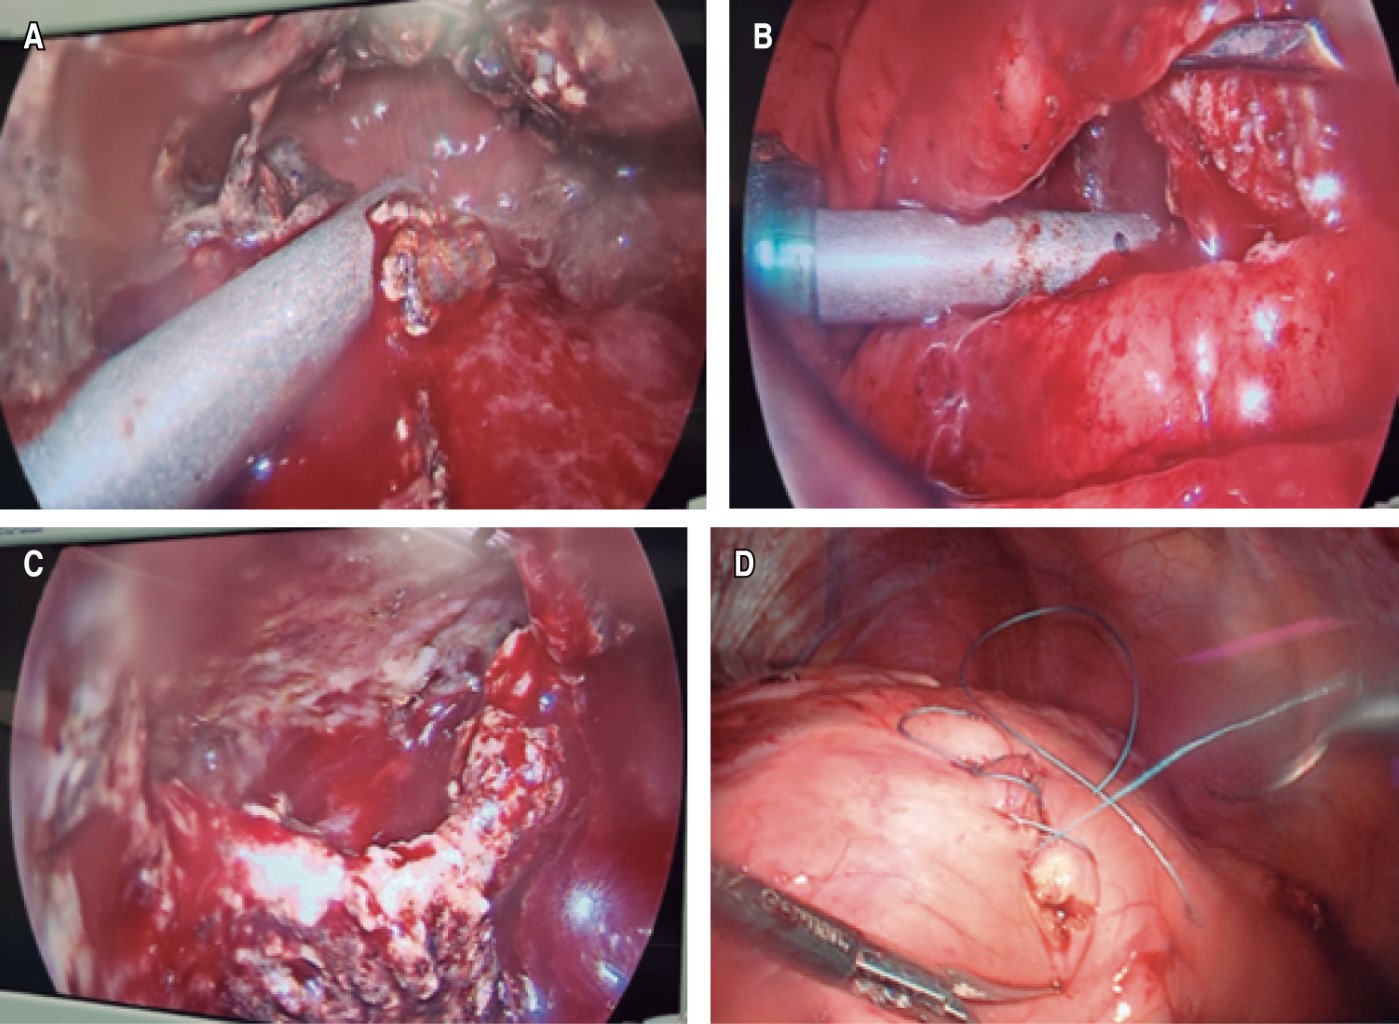

A 48-year-old male patient with a history of smoking (TI of 23), intense alcoholism, marijuana use, hepatitis C, and a history of two events of mild acute pancreatitis of alcoholic origin resolved without apparent complications. Two and a half months later, he came to the emergency department for abdominal pain, presenting hyporexia, nausea, and vomiting after two days of evolution, finding on physical examination pain and increased volume on palpation at the epigastric level located at deep planes, with no evidence of peritoneal irritation. The diagnostic protocol was completed documenting moderately severe acute alcoholic pancreatitis. A computed axial tomography (CT) scan showed evidence of hypodense and irregular image measuring 13.47 × 12.41 × 8.53 cm, with a defined wall and heterogeneous content corresponding to a pancreatic pseudocyst of 746 ml of volume (Figure 1). He started with supportive management until the remission of acute pancreatitis. Laparoendoscopic cystogastric bypass was performed, with findings of a pancreatic pseudocyst with septated necrotic content, which displaced the stomach, obtaining a total of 700 mL of cloudy liquid and detritus (Figure 2). A triple lumen nasojejunal tube was placed for immediate enteral feeding and gastric decompression. The patient was discharged in two days from the General Surgery Service of the Centenario Hospital "Miguel Hidalgo" with a nasojejunal tube and outpatient control, which was removed three weeks after the surgical event, adequately tolerating the oral route.

In the present case, the surgical plan consisted of a laparoscopic procedure with an endoscopic variant, internal drainage, and transgastric pancreatic necrosectomy (Figure 3): a 10 mm transumbilical optical trocar was placed under the Hasson technique, followed by a pneumoperitoneum at 12 mmHg and two working ports in the subcostal region: right 10 mm and left 5 mm. If the left lobe of the liver is very prominent, a 5 mm trocar can be used in the epigastric region with a hepatic retractor (Figure 4). Anterior gastrotomies were performed for the introduction of transgastric trocars, insufflation of the gastric chamber with CO2 for endoscopic vision, a 6 cm posterior gastrotomy at the site of contact with the pancreatic cyst for the performance of cystogastric bypass was performed, ending with curettage and aspiration of the cystic cavity for the extraction of necrotic tissue and detritus. In the end, trocars were removed to the peritoneal cavity for gastrorrhaphy with 2-0 vicryl cross stitches (Figure 2); a soft drainage of the Penrose type was placed towards the surgical bed, and trocars were removed for subsequent closure of the abdominal wall in the usual way.

Figure 2